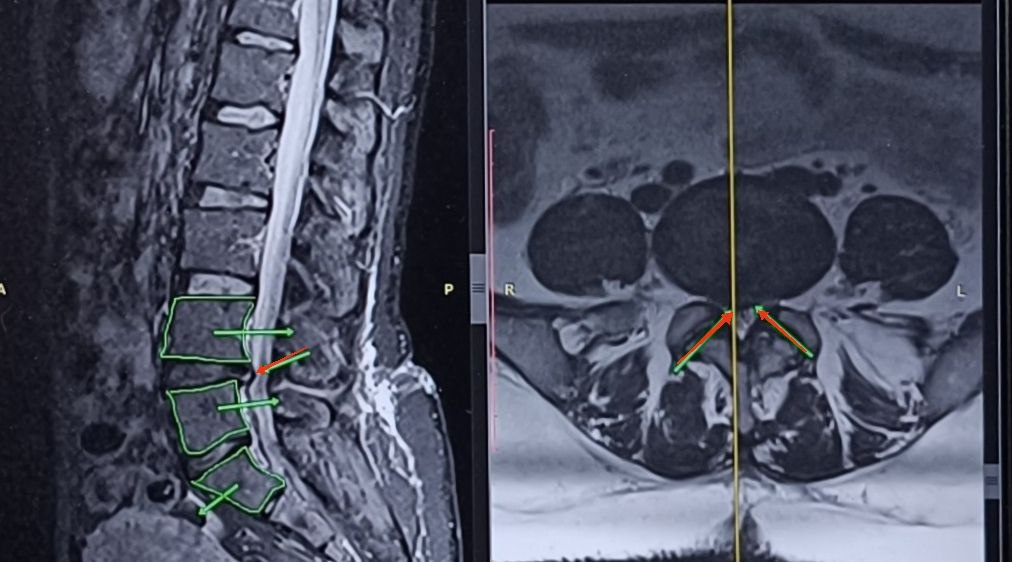

Ее МРТ на фото выше👆 Постоянная боль в правой ноге с июня 2025 года. Боль появилась после операции по удалению грыжи на уровне L4–L5. В июне 2025 грыжу прооперировали. Через время — рецидив на том же уровне. За плечами: — несколько стероидных блокад — физиолечение — пиявки — остеопат — ЛФК Без существенного улучшения. И главный вопрос, с которым она пришла: Оперироваться снова или нет? Как думаете? Разберём факты. Что настораживает в сторону повторной операции: — Хроническая, постоянная боль. А это значит, что нервная система уже стала гиперчувствительной. Даже после операции боль может сохраниться. — Ткани вокруг грыжи находятся в состоянии хронического воспаления. — Сопутствующие состояния: синдром раздражённого кишечника, бессонница, депрессия, избыточный вес. Это системные факторы, которые ухудшают восстановление.Что не в пользу «простого» консервативного пути: — Рецидив грыжи. — Смещение позвонков (листез) — нестабильный сегмент. — Грыжа расположена под связкой — труд

Ее МРТ на фото выше👆